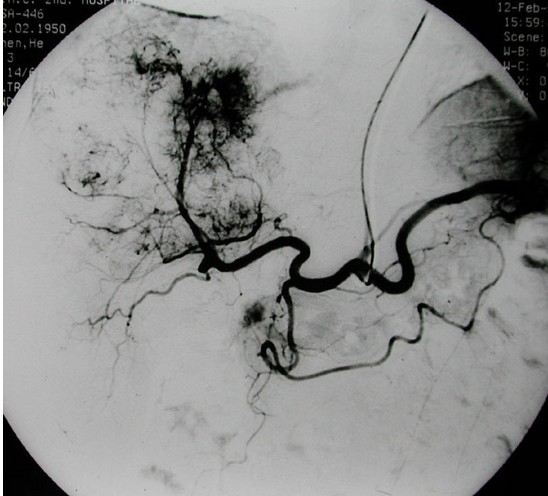

肝动脉栓塞术,最多用于手术不能切除的肝癌,也有用于肝血管瘤、肝动静脉瘘等肝脏疾病。

自1975年有学者报告经导管肝动脉栓塞术(transcatheter arterial embolization. TAE)治疗原发性肝癌以来,到目前已有很大改进。栓塞剂有:超液化碘油、明胶海绵、无水乙醇、碘油乳剂、各种中西药微球微囊等,可与抗癌药混合,利用不同方法经肝动脉灌注以阻断肿瘤的动脉血供、引起肿瘤坏死,同时使局部高浓度的化疗药物缓慢释放、较长时间作用于肿瘤细胞,杀灭肝癌细胞或抑制肝癌细胞生长,而化疗药物的全身毒性作用相对较小。

常用的栓塞途径有:经股动脉穿刺插管至肝固有动脉或肝动脉进行化疗栓塞术;经锁骨下动脉插管法等。